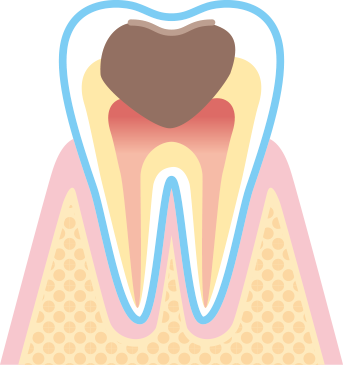

虫歯の過程を分かりやすく説明する表記を専門用語で虫歯を指す「カリエス」の頭文字”C”を用いてC0~C4と段階が付けられています。

段階によって治療内容も変わってきますので参考になさってください。

エナメル質から象牙質に達し状態です。

痛みはあまりありませんが冷たいものがしみ始めます。

インレー(患部を削ったあとの被せ物)やクラウン(患部を削ったあとの冠状被せ物) などの詰め物、被せ物の治療が必要です。